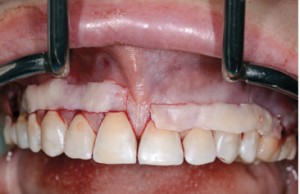

| Zabieg pokrycia recesji w okolicy zębów 16-26 dwoma przeszczepami tkanki łącznej. Przed zabiegiem odbudowano CEJ w tych zębach, w których doszło do jego zniszczenia |

| Status tkanek miękkich po zakończeniu interdyscyplinarnego leczenia ortodontyczno-periodontologicznego | ||